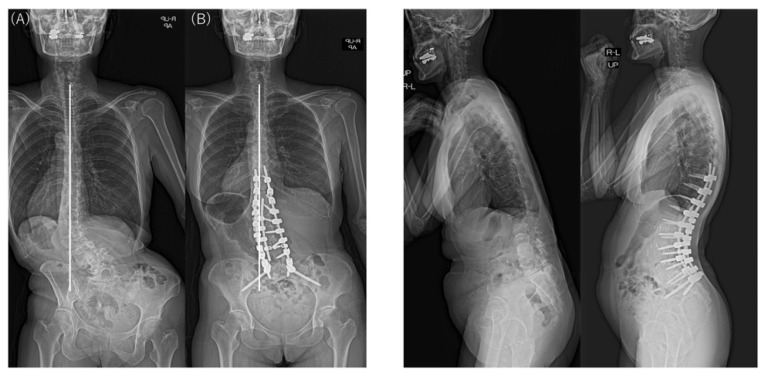

In the examination of the radiographic sagittal parameters across the entire cohort, we found significant improvements in PI–LL, including SVA, LL, and PT. However, TK and PJA increased postoperatively. The major Cobb angle was corrected markedly from 48.8° preoperatively to 13.2° postoperatively (p < 0.001). L4 coronal tilt improved significantly from 18.6° preoperatively to 8.7° postoperatively (p < 0.001) and L5 coronal tilt from 12.9° preoperatively to 7.3° postoperatively (p < 0.001). The major Cobb angle and L4 and L5 coronal tilts also improved in both groups. However, the L4 and L5 coronal tilt were larger before and after surgery in the Obeid type 2 group than in the Obeid type 1A group. The │CBD│ did not differ significantly between the type 1A and type 2A groups before and after surgery. In patients with Obeid type 1A, the │CBD│ changed from 78.4 mm before to 22.8 mm after surgery (p < 0.001). In patients with Obeid type 2A, the change in the │CBD│ from 46.9 mm to 38.5 mm was not significant (p = 0.506) (Table 3).

Analysis of the change or correction (Δ) for each spinal parameter showed a significant difference in ΔTK for the sagittal parameter TK. ΔTK was larger in patients with Obeid type 2A, but other sagittal parameters did not differ significantly between groups. Δ│CBD│ was significantly larger in patients with Obeid type 1A than those with Obeid type 2A (76.6 mm vs. 24.1 mm; p < 0.001) (Table 4).

There were no significant intergroup differences in the changes in the major Cobb angle, correction of coronal tilts of L4 and L5, and the PJA (Table 4). CM was found in 29 of 34 patients with SRS–Schwab type L ASD preoperatively and remained in 12 of these patients at the final follow-up. At the final follow-up, 58.6% (17/29) of patients with SRS–Schwab type L CM showed improvement in CM after corrective fusion using LLIF. Although the difference was not statistically significant, CM improved in 69.6% of patients with Obeid type 1A CM but only 16.7% of those with Obeid type 2A CM (p = 0.056) (Table 5).

Typical postoperative changes are shown in Figure 2, Figure 3 and Figure 4.

All patients received LLIF as the spinal correction surgery in this study. In the sagittal plane, it was suggested that CM types did not affect SRS–Schwab assessment factors ΔSVA, ΔPT, and ΔPI-LL. LLIF and posterior corrective fusion corrected the preoperative CM in nearly 70% of patients with Obeid type 1A. However, using LLIF to correct the CM deformity in the coronal plane in a patient with Obeid type 2A may worsen the main lumbar curve by causing malalignment toward the convex side (Figure 5 and Figure 6).